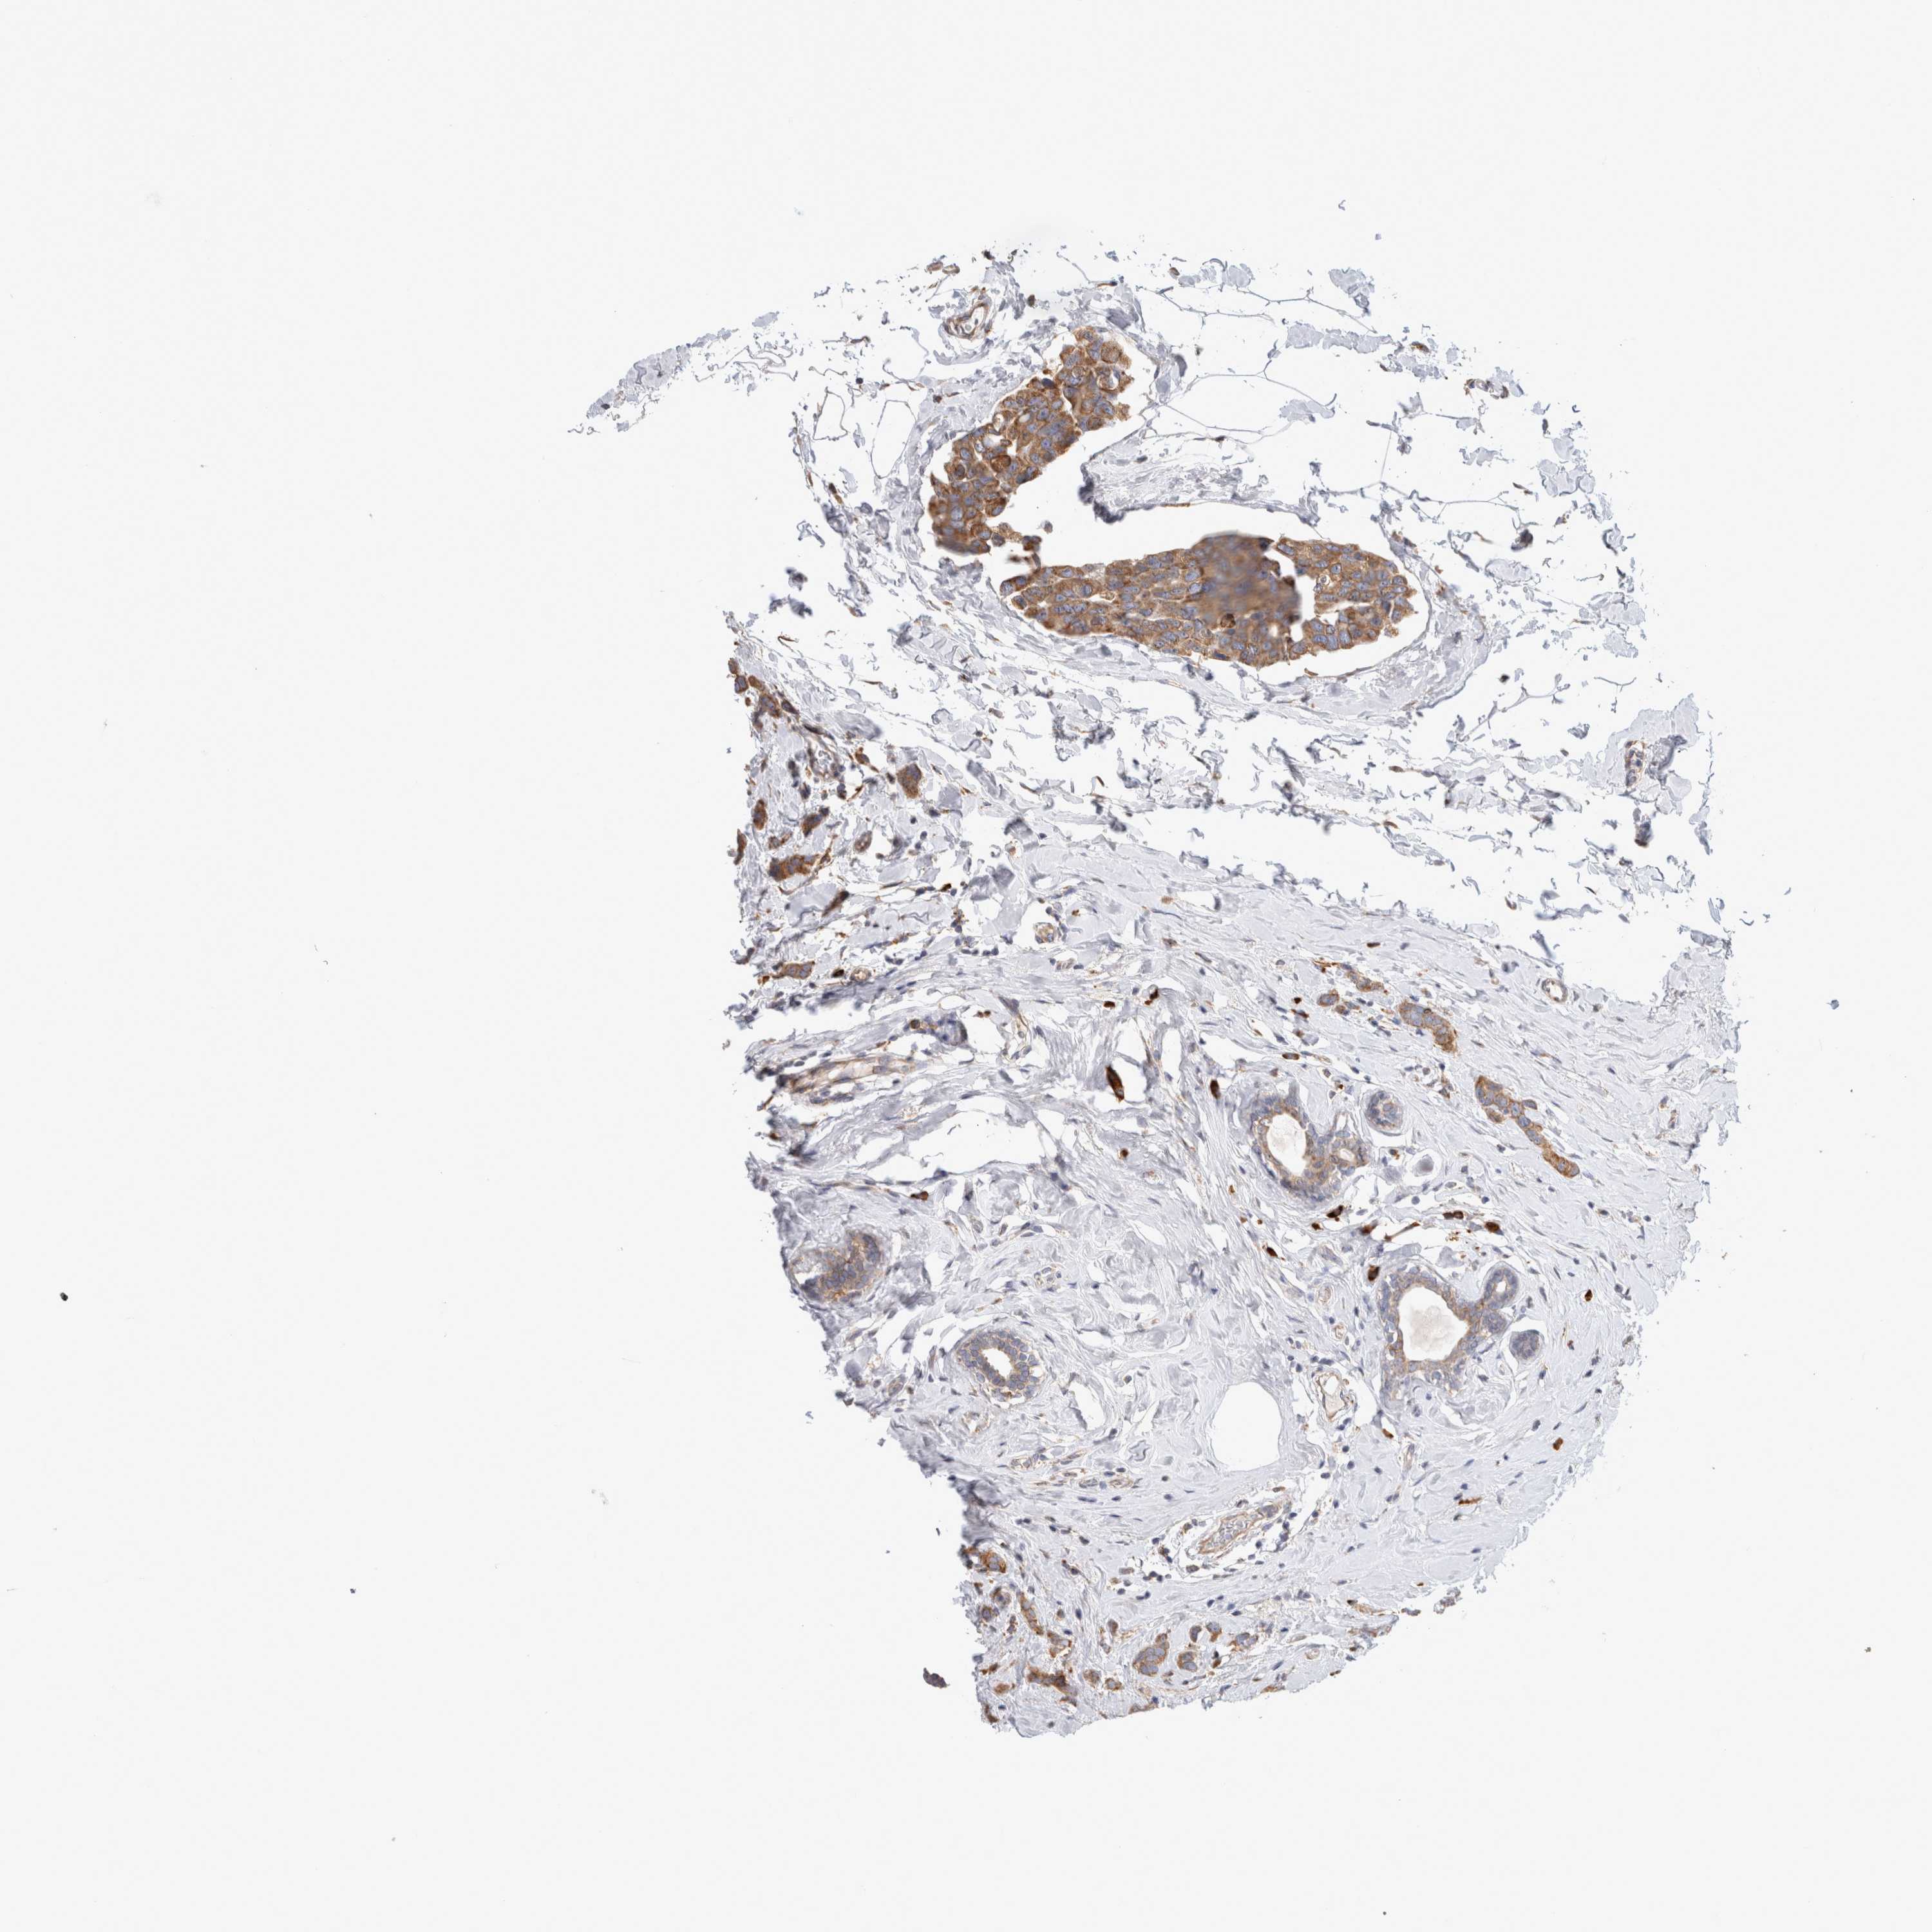

CANCER BREAST CANCER Show tissue menu

BRCA TCGA BRCA VALIDATION PROTEIN EXPRESSION

ANTIBODIES

AND

VALIDATION